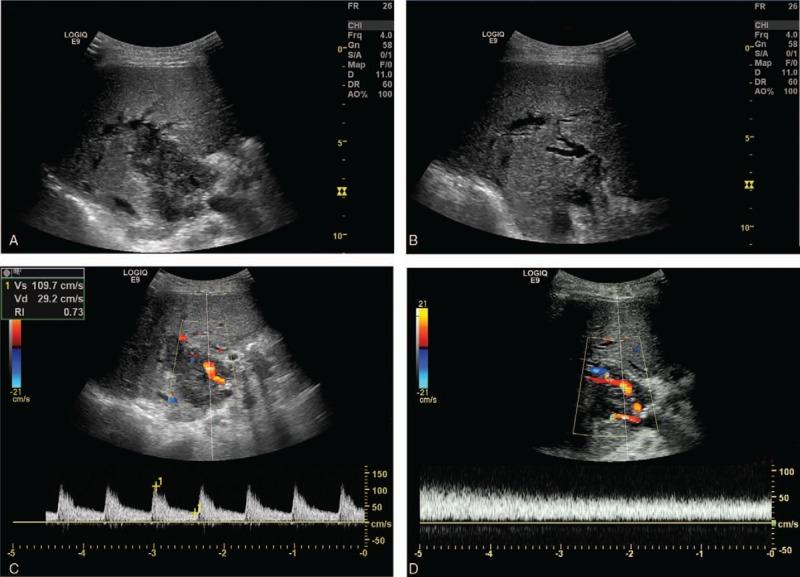

Laboratory examination showed impaired liver and renal functions and Epstein-Barr virus (EBV) infection, but tumor markers within normal ranges. Gastroscopy showed esophageal varices. Ultrasound and computed tomography angiography revealed an ill-defined and irregular solitary lesion in the porta hepatis, encasing both the portal vein and the hepatic artery. The lesion was characterized by arterial hyper-enhancement and hypo-enhancement in the remaining phases with contrast-enhanced ultrasound (CEUS). The lesion was finally confirmed as an IMT by ultrasound-guided biopsy.

实验室检查显示肝肾功能受损及EB病毒(EBV)感染,但肿瘤标志物在正常范围内。胃镜检查显示食管静脉曲张。超声和计算机断层血管造影显示肝门处有一个边界不清、不规则的孤立性病变,包绕门静脉和肝动脉。对比增强超声(CEUS)显示该病变动脉期呈高增强,其余期呈低增强。最终经超声引导下活检确诊为IMT。